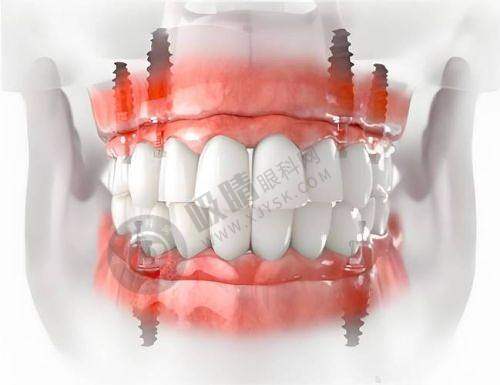

陕西省人民医院口腔科可开展全口数字化种植、ONLY 植骨术、骨劈开术、GBR 手术、即刻种植、上颌窦外提升等高难度的种植技术。

西安交通大学医学校第一附属医院口腔科引入机器人种植(5 分钟/颗)、3D 导板设计,减少人力与耗材浪费;提供3D 数字化模拟矫正方案,提前预览牙齿移动轨迹。

西安交大口腔正畸科提供3D 数字化方案设计,修复科引进德国即刻种植技术

西安瑞泰口腔医院配备数字化等设备,确保诊疗过程的精细与安心,开展种植牙、牙齿矫正等特色项目。